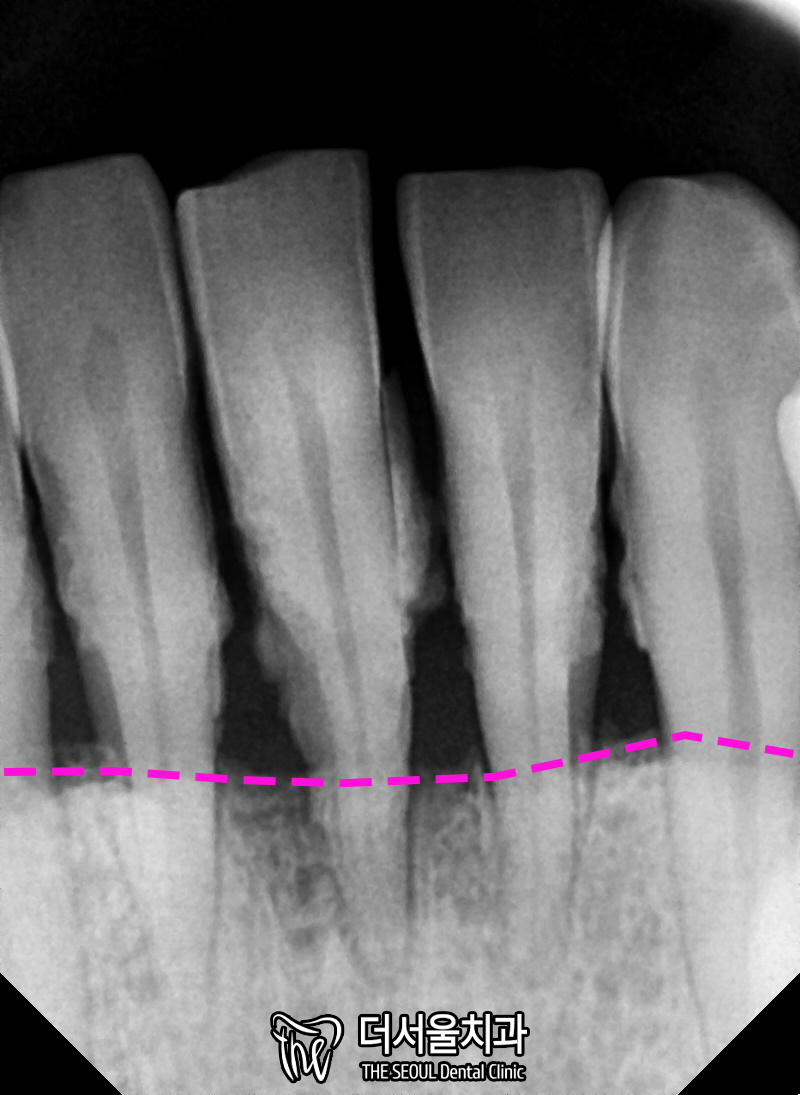

또, 전반적으로 남아있는 잇몸뼈를 보면,

고르지 않고 울퉁불퉁 합니다.

특히 아래 부분이 심각합니다.

스케일링으로 치석을 제거하고

엑스레이를 한번 더 찍어보면,

이렇게 뿌리 끝만 잡고 있을 정도로

남아있는 뼈가 없는 상태였습니다.

그러니 흔들림이 클 수밖에 없구요.